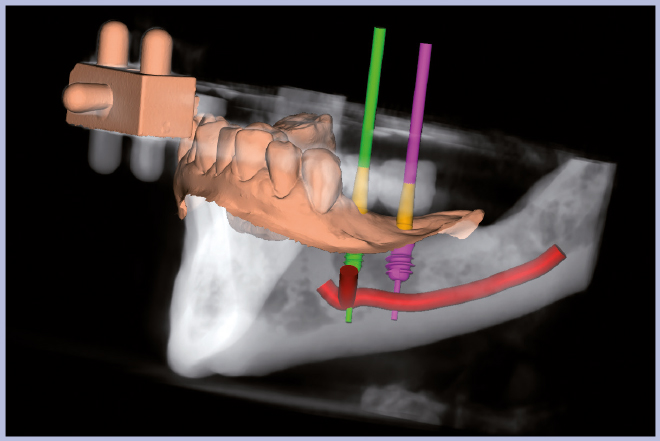

- Figg. 8-12 – Pianificazione implantare con software 3Diagnosys Leone

- Fig. 9

- Fig. 10

- Fig. 11

- Fig. 12